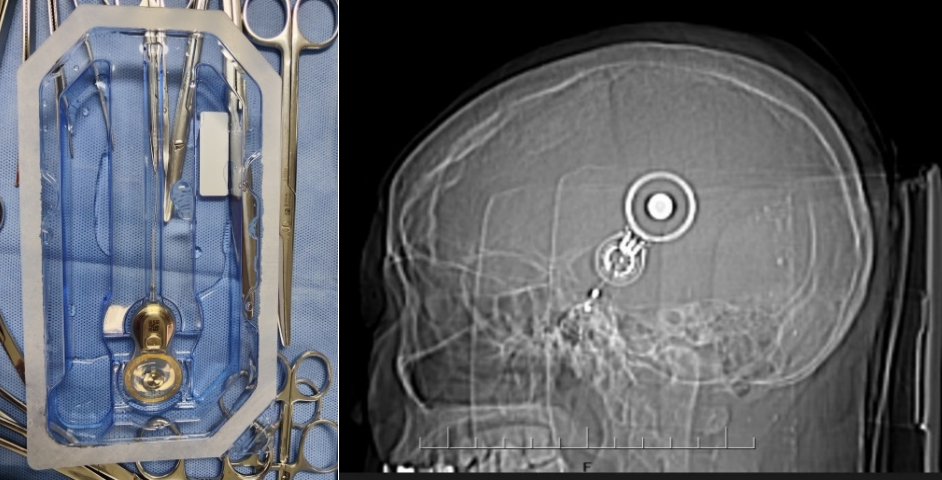

入院后,亚洲色吧 附二院耳鼻咽喉科专家团队对徐某进行了全面细致的检查和评估,结合他的具体情况,制定了个性化的手术方案。手术过程顺利,成功将集采的人工耳蜗植入徐某耳内,术中神经电生理监测,耳蜗电极均正常工作,术后耳蜗CT显示电极位置正确。术后,经过医护人员精心护理和康复指导,徐某恢复良好,各项指标正常,顺利出院。主刀医生白忠主任叮嘱患者,1个月后返院,人工耳蜗开机后,患者就可以听到声音了,恢复有声世界。

据亚洲色吧 附二院耳鼻咽喉科专家白忠主任医师介绍,人工耳蜗是一种电子装置,通过植入体内的电极系统直接刺激听神经,帮助重度、极重度感音神经性耳聋患者恢复听力。以往,人工耳蜗价格高昂,让许多患者望而却步。此次国家集采政策落地云南后,人工耳蜗价格大幅下降,极大减轻了患者的经济负担,让更多听障患者有机会接受治疗,重获听力。